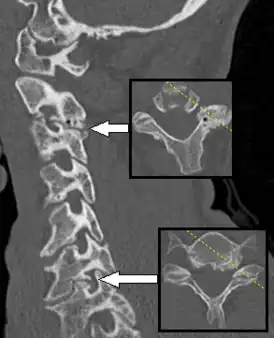

![]() КТ Спондилёза, вызывающий радикулопатию | |

Диагностируется по наличию клинических симптомов, обнаружении сдавливания корешков с помощью МРТ и КТ. Существует множество способов лечения: лечебная гимнастика, физиотерапия, различные лекарственные препараты и хирургические операции.